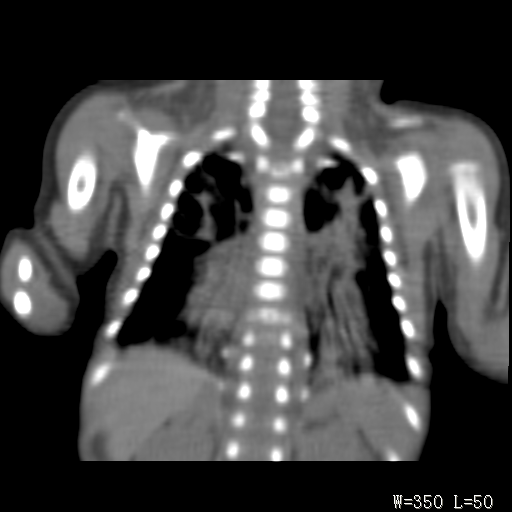

以下是引用改行者在2010-7-8 22:13:00的发言:[br]两肺野透光度降低伴细颗粒状影,两肺下叶见实变影,其内见支气管充气征。 多考虑新生儿肺透明膜病。